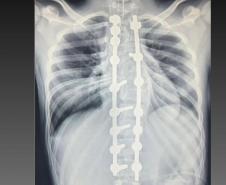

Laura era portadora de escoliose e, em agosto de 2025, realizou a cirurgia de correção da coluna, o que lhe permitirá ter uma vida normal de agora em diante. Moradora de Bom Sucesso do Sul, região Oeste do Paraná, é acostumada a andar a cavalo, mas com o problema na coluna a prática estava longe de ser prazerosa.

A cirurgia ocorreu no dia 28 de julho e uma segunda etapa em quatro de agosto. Desde então, Joyce viu a sua vida mudar. “Nasci com a escoliose e tinha muita dificuldade e limitações para caminhar e perda de movimento. Havia dias em que eu não levantava da cama. Quando saia de casa recebia olhares de julgamento das pessoas, que era o que mais me incomodava. Depois da cirurgia, posso dizer que eu tenho uma nova vida. Eu venci a batalha”, relatou.